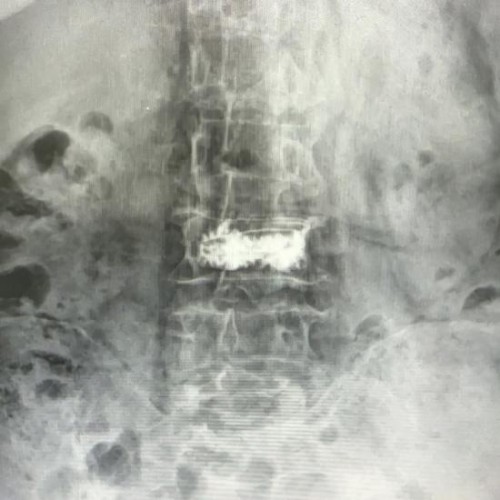

面对家属“希望老人尽快摆脱疼痛、重新站起来”的迫切愿望,骨科主任高胜一迅速组织多学科会诊。团队结合患者影像学检查结果、全身状况综合评估,在充分与家属沟通手术风险与预期获益后,最终确定采用经皮椎体后凸成形术(PKP)方案。该手术具有创伤小、恢复快的优势,通过背部小切口,在影像设备精准定位下插入球囊扩张器恢复椎体高度,再注入骨水泥稳定椎体结构,可有效缓解疼痛并避免长期卧床并发症。

经详细术前评估与充分准备,手术当日,高胜一与副主任医师杨兆平紧密配合,顺利穿刺并注入骨水泥,整个操作过程精细流畅,耗时约30分钟。王奶奶麻醉苏醒后,便明显感觉到折磨多日的腰背剧痛大幅减轻。次日,在医护人员指导下,老人顺利下床行走,有效避免了长期卧床可能引发的各类并发症。看着老人重新露出的笑容,家属悬着的心终于落了地。目前王奶奶已顺利康复出院,回归正常的家庭生活。